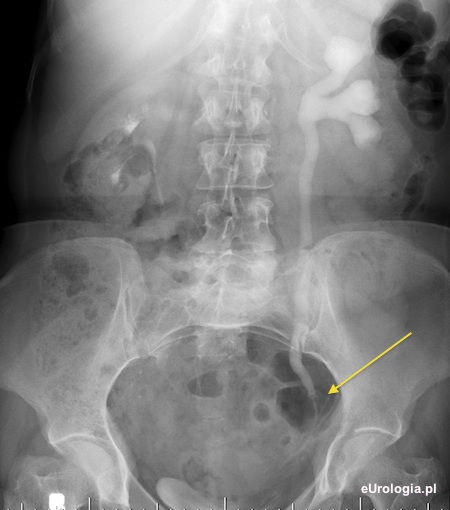

Fot. Poszerzony układ kielichowo - miedniczkowy nerki i moczoód w wysokości 6 mm złogu (miejsce zanaczone strzałką).